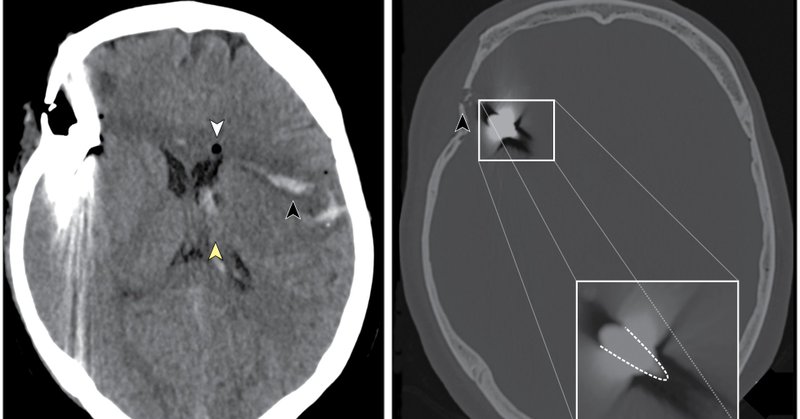

A 65-year-old man with uncontrolled hypertension, coronary artery disease and heavy smoking presented to the emergency department with somnolence and left-sided hemiplegia. Earn #CME and learn more about this case with @JAMANeuro.

This case report describes a 65-year-old man with a mobile filling defect detected in his middle cerebral artery during mechanical thrombectomy.